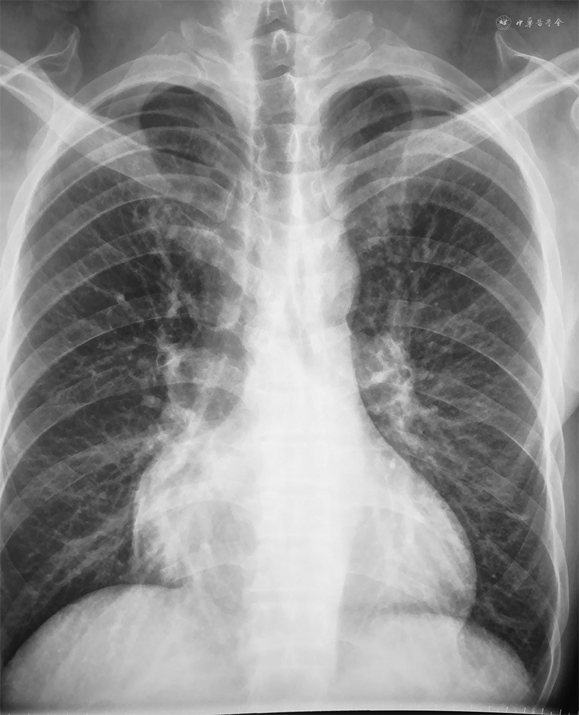

患者男性,41岁,主因“劳力性气短1月,加重1周”于2019年7月17日入院。2019年6月初活动后出现气短,不伴胸闷、胸痛、咽喉部紧缩感及肩背部放射痛,稍事休息可缓解,未诊治。7月10日起气短加重,劳动耐量较前下降,稍活动即感气短,平卧位时亦有气短发作,坐起后可缓解,不伴尿量减少、腹胀及双下肢水肿,为明确诊治来诊。既往史:否认高血压、糖尿病史。2019年4月15日因发热、咳嗽,最高体温为38.4 ℃,于外院行胸部CT示右肺中叶及左肺下叶炎性病灶,部分纤维化,少量心包积液,予抗感染、止咳等治疗后发热、咳嗽缓解。5月10日因左侧头疼伴左半身麻木、呃逆、呕吐行头颅磁共振成像(magnetic resonance imaging,MRI)检查提示急性脑梗死,经改善脑循环、脑保护、稳斑等治疗,无明显后遗症。个人史:吸烟史20年,平均20支/日。入院查体:神志清楚,半卧位,血压100/60 mmHg(1 mmHg=0.133 kPa),颈静脉无怒张,双肺呼吸音清,未闻及干、湿性啰音。心率105次/分,律齐,P2>A2,各瓣膜听诊区未闻及病理性杂音,移动性浊音阴性,双下肢无水肿。心电图:心率96次/分,V1-V4导联R波递增不良(图1)。胸片:双肺纹理增重,心界扩大(图2)。血常规、肝肾功能、电解质、凝血正常范围。心肌肌钙蛋白I(cardiac troponin I,cTnI)0.06 ng/mL,N末端B型利钠肽前体(N terminal-pro B type natriuretic peptide,NT-proBNP)6645.9 pg/mL。动脉血气分析:酸碱度(pH)7.409,二氧化碳分压(PCO2)33.5 mmHg,氧分压(PO2)70.4 mmHg。冠状动脉造影示:未见斑块及有意义狭窄。超声心动图示(图3):双心房增大,左心室、右心室稍大,左心室壁稍增厚,右心室壁厚约3.5 mm。二尖瓣舒张期血流频谱呈双峰,E/A>2。估测肺动脉收缩压约为37 mmHg,左心室射血分数32%,缩短分数15%,左心室舒张末期容积128mL,左心室收缩末期容积87mL,每搏量41mL,心输出量3.18L/min。心脏MRI检查示(图4):双心房增大,左心室壁稍厚,心肌首过灌注示未见明显异常灌注减低或缺损,延迟扫描示室间隔中段可见壁间线状强化,左心室下壁、侧壁及右心室游离壁可见广泛心内膜下强化。心内膜活检及心肌免疫组化示(图5):心肌细胞轻度肥大,心肌细胞间可见淀粉样物质沉积,刚果红染色(+),轻链λ(+),甲状腺素转运蛋白(transthyretin,TTR)(+)。血清免疫球蛋白测定示血清游离轻链(serum free light chain,sFLC)κ 7.67 mg/mL,λ 97.5 mg/mL↑,λ/κ比值(12.7)明显升高。尿本周蛋白:轻链κ 6.63 mg/L,轻链λ 3.66 mg/L。骨髓象及活检(图6):间质内浆细胞散在或灶性浸润(CD138+,κ-,λ+,VS38c+,MUC1散在+,约占15%),局灶可疑有淀粉样物质沉积(刚果红染色弱阳性)。骨髓流式:CD38+CD138+CD27+,轻链λ限制性表达。全身低剂量CT平扫示:颅骨、肩胛骨、肱骨、肋骨、颈、胸椎椎体、骶骨、髂骨、股骨等部位骨皮质变薄,骨小梁稀疏。据上述结果最后确诊为“多发性骨髓瘤、限制型心肌病(心肌淀粉样变)、心功能Ⅳ级(NYHA分级)”。入院后予口服螺内酯20 mg,1次/d,呋塞米10 mg,1次/d,贝前列素钠40 μg,3次/d,比索洛尔片5 mg,1次/d,辅酶Q10,10 mg,3次/d及重组人B型利钠肽治疗,气短症状明显缓解,夜间平卧位休息。后行BD方案(硼替佐米、地塞米松)化疗,化疗第3日患者心功能突发恶化,不能平卧,伴腹胀及双下肢浮肿,遂停止化疗,再次予重组人脑利钠肽及利尿治疗后心能明显改善,可耐受日常活动及平卧位,后症状好转后出院。院外患者规律口服贝前列素钠、螺内酯、呋塞米、比索洛尔等药物治疗,但2020年3月15日于院外猝死。

限制型心肌病(RCM)是一种室壁僵硬度升高导致心室舒张功能显著下降为特点的心肌疾病,属混合型心肌病,可分为特发性、家族性或继发于不同的系统性疾病。其诊断依据为:心室限制性舒张功能障碍,伴一侧或双侧心室舒张末期容积或收缩末期容积正常或缩小,室壁厚度正常,并除外缺血性心肌病、心脏瓣膜病、心包疾病和先天性心脏疾病[1]。临床表现为左和(或)右心衰竭,如乏力、气短、体力活动受限、水肿、晕厥、栓塞或各种心律失常等。心电图可有巨大P波、传导阻滞、低电压或R波递增不良表现。超声心动图是最重要的检查手段之一,二维超声心动图其特点为心房增大,心室正常或缩小,部分患者表现为巨大心房。M型超声表现为室壁偏厚,活动明显减低,舒张期左心室内径变小,容积减小,射血分数及短轴缩短率明显减小。多普勒超声可见二尖瓣、三尖瓣关闭不全,二尖瓣口血流呈限制性充盈障碍表现,E峰高尖,E/A>2,E波减速时间缩短,等容舒张时间缩短等。心脏MRI检查是超声心动图的重要补充,除有助于同缩窄性心包炎鉴别外,结合钆显像可明确RCM的分类[2]。本例患者以劳力性气短、不能平卧就诊,化验NT-proBNP水平升高,符合左心功能不全表现。心电图提示左房增大,伴V1-V4导联R波递增不良,超声心动图提示双心房增大、E/A>2,符合限制型充盈障碍表现。超声心动图提示左心室壁可见点状强回声,结合心脏MRI晚期钆增强,心肌活检刚果红染色阳性可确诊RCM、心肌淀粉样变(cardiac amyloidosis,CA)。